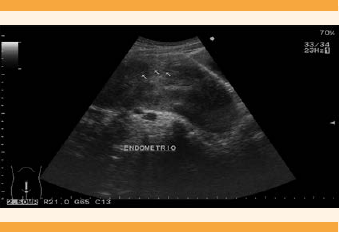

El primer ultrasonido pélvico informó: útero en anteversión, ligeramente inclinado a la derecha, piriforme, con bordes ligeramente lobulados, de 152.5 x 70.9 x 103.8 mm; patrón ecográfico heterogéneo a expensas de varias lesiones sugerentes de miomatosis de medianos elementos. La ecografía endometrial, central y lineal con espesor de 14.1 mm. El ovario derecho midió 41.4 x 23.6 x 30.9 mm, con volumen de 15.8 cc; patrón folicular normal. El ovario izquierdo: 33 x 23.9 x 24.4 mm, con 10.3 cc y patrón folicular normal. Las imágenes coincidieron con miomas de predominio intramural de medianos elementos.

El segundo ultrasonido pélvico reportó: útero en anteflexión con aumento de volumen, bordes regulares definidos, de 16.8 x 7.2 x 13.2 cm; miometrio con ecogenicidad heterogénea a expensas de múltiples imágenes hipoecoicas ovaladas y redondeadas, bien delimitadas, de diferente tamaño y diseminadas en esta zona, de 5.6 x 2.4 cm, 2.6 x 1.2 cm, 1.8 x 1.4 cm, 2.6 x 1.6 cm y 3.2 x 2.1 cm. La cavidad endometrial central, ecogénica y lineal. El ovario derecho se apreció de forma, tamaño y situación normal, de bordes regulares, definidos, de 48 x 27 x 37 mm, con volumen de 24.7 cc, incluido un quiste de 24 x 14 mm. El ovario izquierdo de tamaño y situación normal, de 26 x 19 x 30 mm, volumen de 8.03 cc y parénquima homogéneo. Se informaron múltiples lesiones hipoecoicas diseminadas en el miometrio, de apariencia metastásica, sin relación con imágenes características de miomas. (Figuras 1 y 2) Debido al súbito incremento de tamaño, comparado con el ultrasonido pélvico previo, se solicitó una tomografía pélvica y determinación de marcadores tumorales. Ésta reportó: hígado con aumento de tamaño del lóbulo izquierdo, densidad conservada; útero de 173 x 76 x 125 mm, con perímetro liso; miometrio de aspecto heterogéneo, a expensas de múltiples lesiones ovoides, bien delimitadas, isodensas, con diámetro mayor de 17-80 mm, de localización dispersa, con predominio en la cara anterosuperior, que comprimían y desviaban el endometrio hacia la derecha. Endometrio lineal, de 5 mm, sin adenopatías ni líquido libre en la cavidad abdomino-pélvica. Se identificaron leiomiomas de tipo intramural de medianos y grandes elementos, ovarios sin lesiones visibles y hepatalgia a expensas del lóbulo izquierdo. (Figura 3) La concentración de marcadores tumorales estuvo dentro de los límites de referencia: Ca-125 30.34 u/mL y deshidrogenasa láctica de 265 u/L.